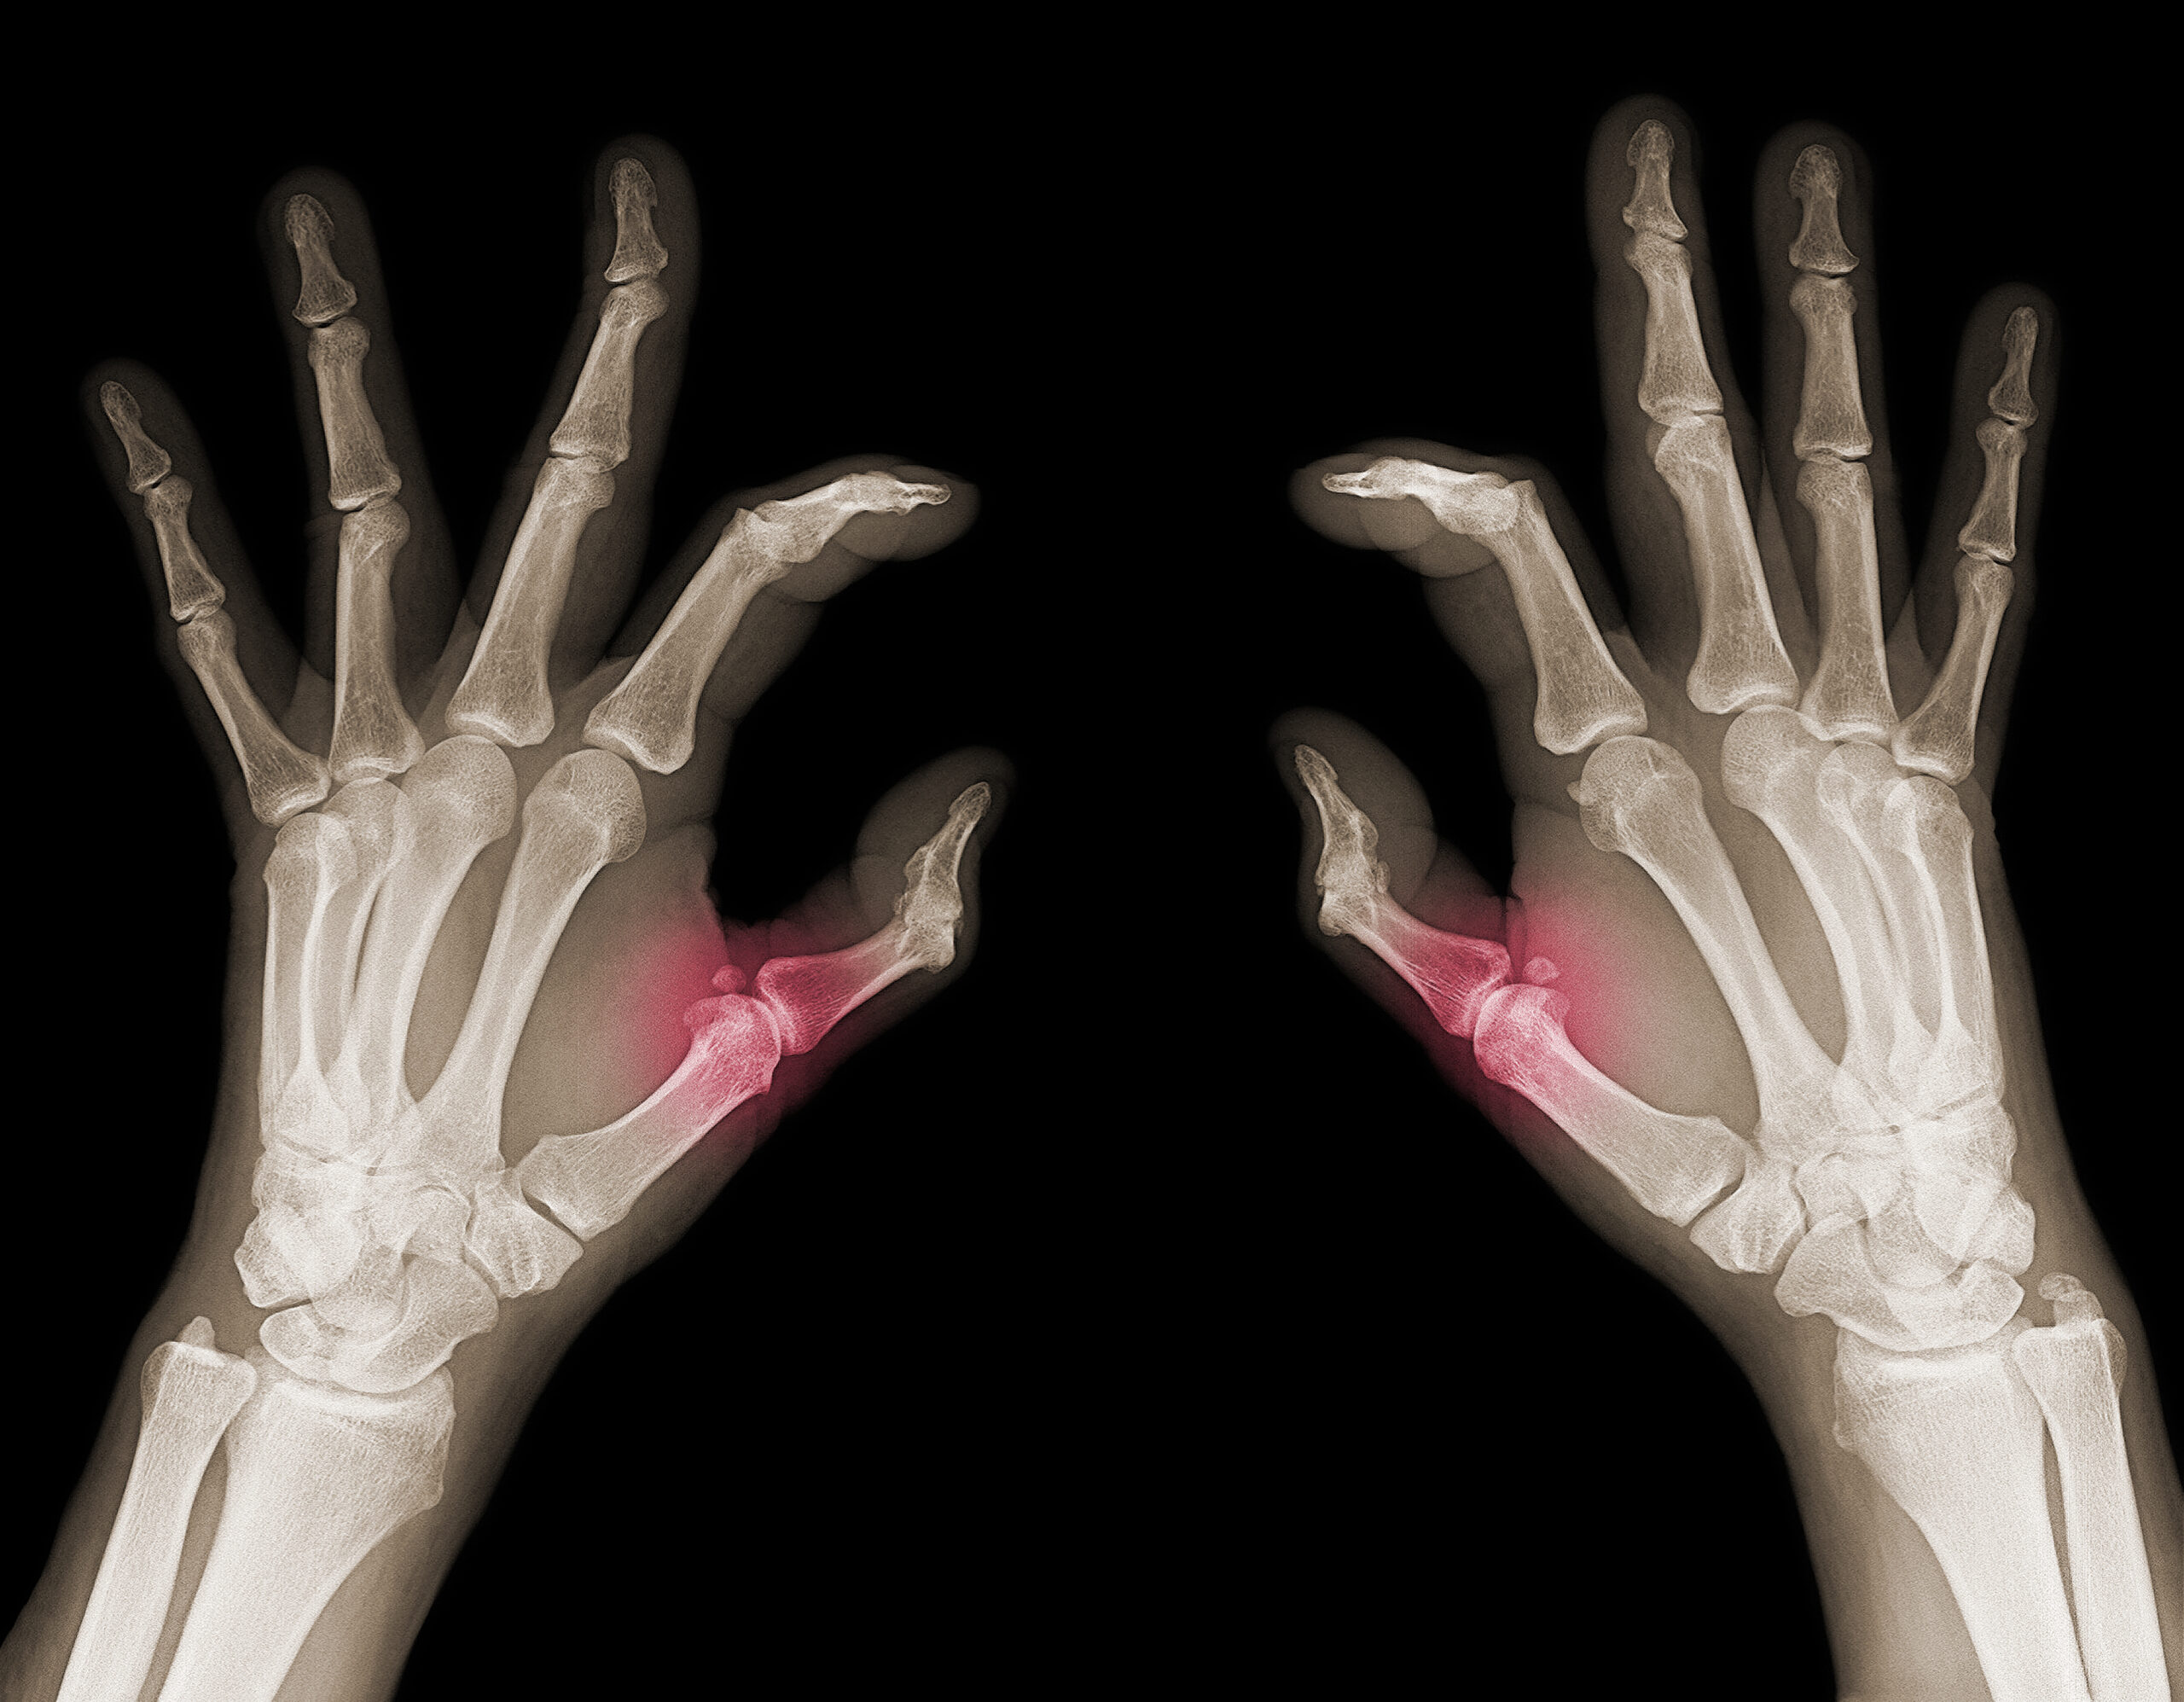

Die Expertinnen und Experten der FAU nehmen in ihrem Projekt unterschiedliche Arten von Strahlung in den Blick, mit denen wir zum Beispiel bei medizinischen Behandlungen in Kontakt kommen oder die in der Natur zu finden sind und ein Risiko für uns darstellen können. Dazu gehört die Röntgenstrahlung, eine ionisierende Strahlung mit der zum Beispiel Tumoren behandelt werden. Hinzu kommt die von Radon ausgehende alpha-Strahlung, die etwa über natürlich vorkommendes Uran entsteht. Von all diesen Strahlungsarten weiß man, dass sie in niedrigen Dosen unter anderem entzündungsmildernd wirken und die Knochenstabilität positiv beeinflussen können, in hohen Mengen jedoch eher Entzündungen fördern und ein Krebsrisiko darstellen.